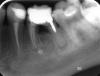

Nataliko Опубликовано 19 ноября, 2008 Поделиться Опубликовано 19 ноября, 2008 Доброго времени суток. Недавно была у стоматолога. В числе прочих, вопрос коснулся непростого зуба.7 лет назад я лечила хронический пульпит нижней 6. Лечение длилось 2 мес., во время лечения зуб сильно болел. Предлагали удалять, но я отказалась. В итоге удалось сделать. В последний визит к стоматологу этот зуб пока не трогали, только сделали рентген. Предложили два варианта: удалить или лечить. Рекомендуют удалять, аргументируют, что лечить сложно, да и результата может не будет.Прошу прокомментировать с профессиональной коллективной точки зрения, стоит ли лечить???Заранее благодарна. Рентген прикреплен к посту. Ссылка на комментарий

Doc Опубликовано 20 ноября, 2008 Поделиться Опубликовано 20 ноября, 2008 Доброго времени суток. Недавно была у стоматолога. В числе прочих, вопрос коснулся непростого зуба.7 лет назад я лечила хронический пульпит нижней 6. Лечение длилось 2 мес., во время лечения зуб сильно болел. Предлагали удалять, но я отказалась. В итоге удалось сделать. В последний визит к стоматологу этот зуб пока не трогали, только сделали рентген. Предложили два варианта: удалить или лечить. Рекомендуют удалять, аргументируют, что лечить сложно, да и результата может не будет.Прошу прокомментировать с профессиональной коллективной точки зрения, стоит ли лечить???Заранее благодарна. Рентген прикреплен к посту. Удалять его нужно было семь лет назад. Те, кто предлагают лечить его сегодня вызывают недоумение. Ссылка на комментарий